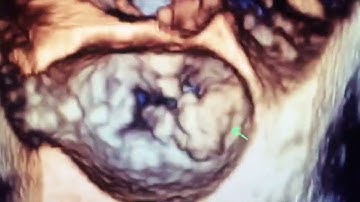

Mitral Annulus Calcification (MAC): Detecting, Grading & Implications